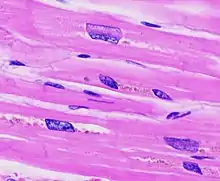

| The diagram shows a typical heart (left) and one with ventricular hypertrophy (right). | |